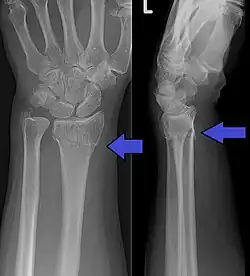

An X-ray showing a Colles' fracture

Colles fracture of the left hand, with posterior displacement clearly visible

Diagnosis can be made upon interpretation of anteroposterior and lateral views alone.[7]